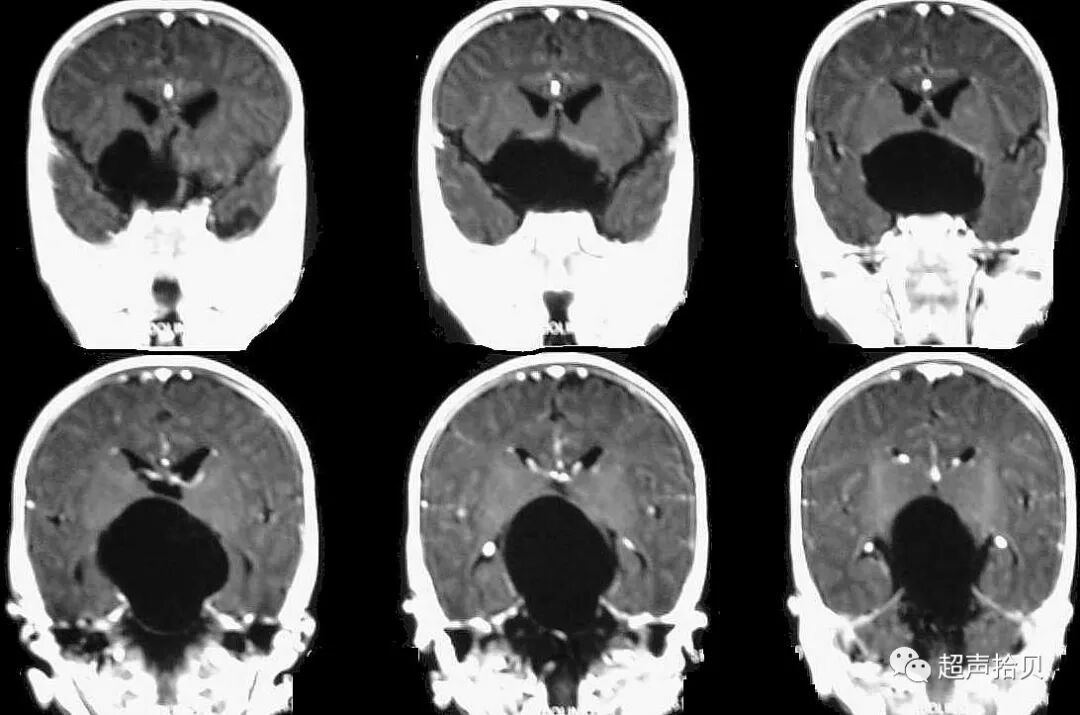

图4:妊娠26周时的产前MRI:第三脑室蛛网膜囊肿的横向(A),矢状(B)和冠状面(C)平面引起脑室扩张

图5:出生后1周进行T1加权轴位MRI扫描。 侧脑室的后角和前角,特别是第三脑室,被蛛网膜囊肿占据。